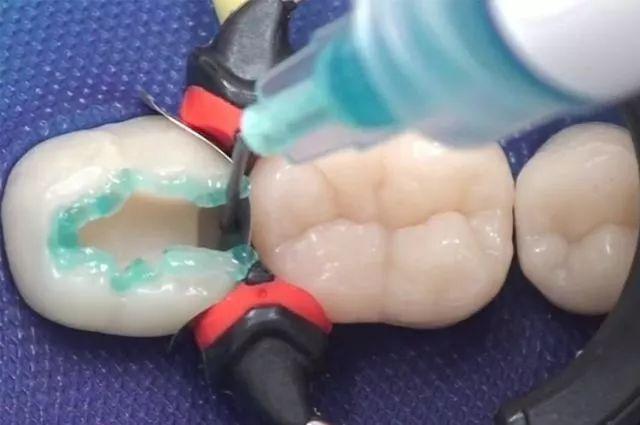

第三步,将补牙的材料填充进制备好的牙洞当中,确保材料和牙齿的接触紧密,然后调整形状,恢复患者的对咬牙高低。

现在我们使用的补牙材料基本上以树脂材料居多,这种材料坚硬耐磨所以能满足绝大多数情况下的口腔使用要求。当然,还有更先进的嵌体修复技术,如果经济上可以承受,也可以进行选择。

不论是用何种补牙手段,制备牙洞都是不可避免的步骤,所以请广大的患者在进行补牙的时候,心中要有数。为了更好的祛除腐坏物质,制备牙洞是不能俭省的过程。